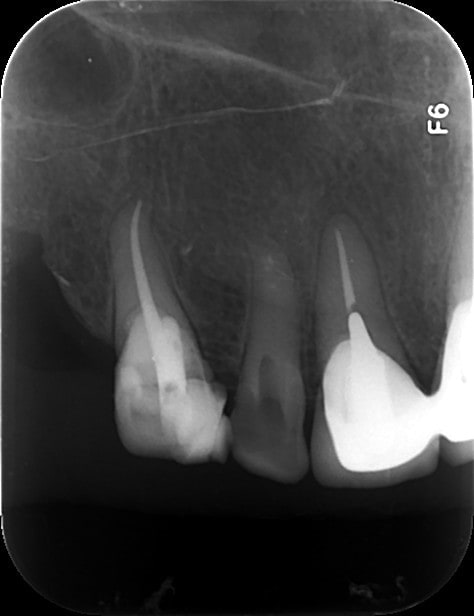

1   02022015 xhyug0 - Eugenol

3   02022015 athoja - Eugenol

2   02022015 jomvv1 - Eugenol

4   06022015 zewfwa - Eugenol

5   06022015 uym87j - Eugenol